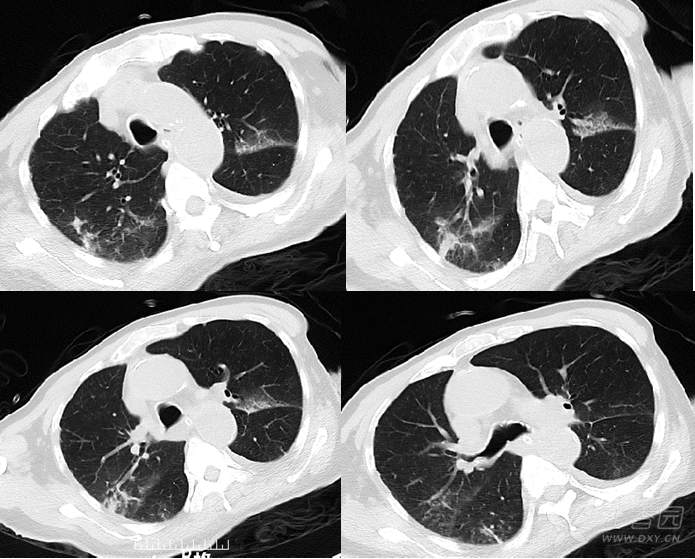

吸烟导致双肺坠积效应先来看一下正常人的胸部ct:胸廓的横径和前后径

图片尺寸640x640